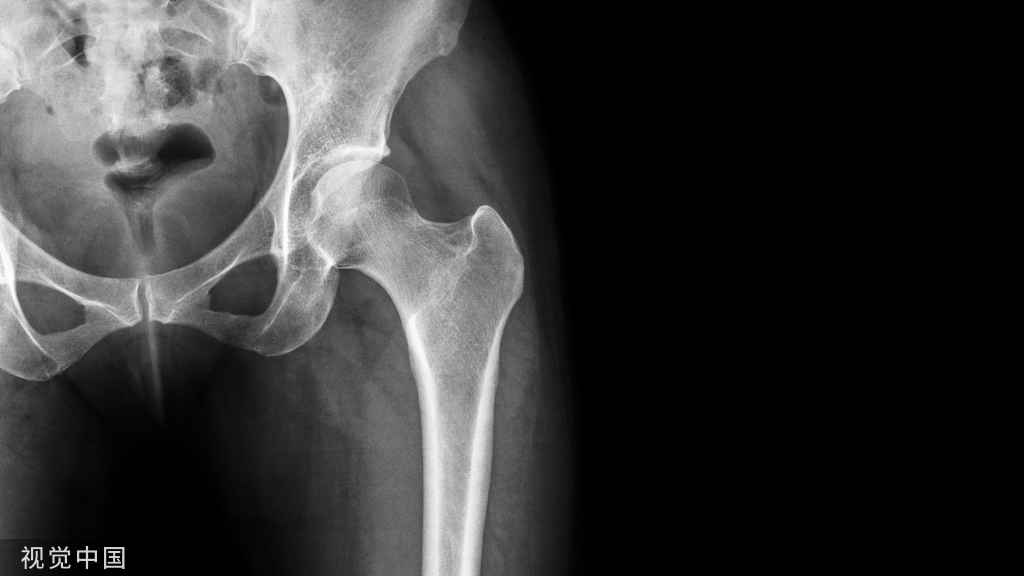

现在对股骨骨折进行牵引时,一般与 Thomas 架整合使用(图 10)。

而牵引远端可采用骨牵引(图 11),或皮牵引(图 12)。

除此之外,在严重髋臼骨折股骨头中央型脱位患者中,可以沿股骨颈轴线方向进行牵引,减少股骨头髋臼中央的压力,并尽量获得一定程度上复位(图 13)。